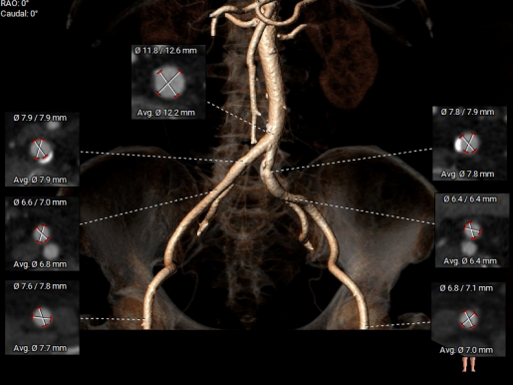

CT测量

主动脉根部CT测量

瓣环周长:90.3mm

LVOT周长:97.1mm

瓣环上4mm:82.7mm

瓣环上6mm:85.6mm

左冠开口高度:21.4mm

右冠开口高度:16.3mm

左窦瓣叶长度:20.8mm

右窦瓣叶长度:19.1mm

STJ周长:129.8mm

升主动脉周长:157.5mm

法氏窦

周长:133.9mm;左冠状窦直径:45.4mm;无冠状窦直径:31.8mm

主动脉瓣钙化积分:787mm2

瓣环周长:73.1mm

LVOT周长:79.3mm

瓣环上4mm:71.2mm

瓣环上6mm:70.4mm

左冠开口高度:7.1mm

右冠开口高度:13.7mm

左窦瓣叶长度:15.2mm

右窦瓣叶长度:16.6mm

STJ周长:88.6mm

升主动脉周长:112.3mm

右冠状窦直径:28.8mm;左冠状窦直径:30.8mm;无冠状窦直径:32.5mm